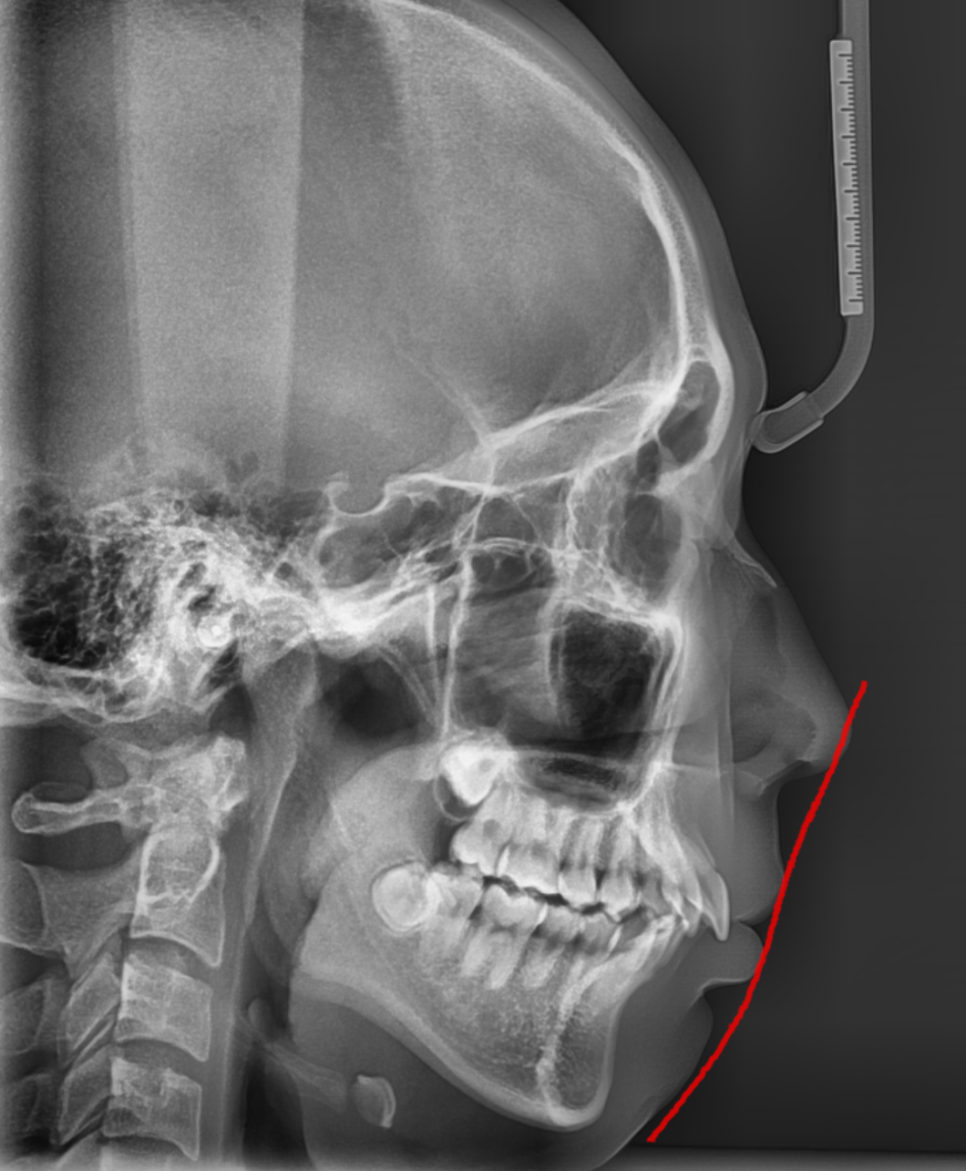

250218 치아 옆 모습을 확인하는 x-ray 그냥 찍는게 아닙니다~

정밀한 엑스레이

얼굴 라인 분석등을 통해 진단됩니다.

턱관절에도 문제가 없는지 판단해야하고요